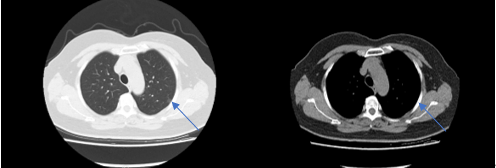

吳阿姨的CT檢查提示左上肺直徑約1cm的肺結(jié)節(jié)

患者行不插管的面罩靜脈全麻

賴主任及其團(tuán)隊(duì)為吳老師行單孔胸腔鏡肺結(jié)節(jié)切除手術(shù)